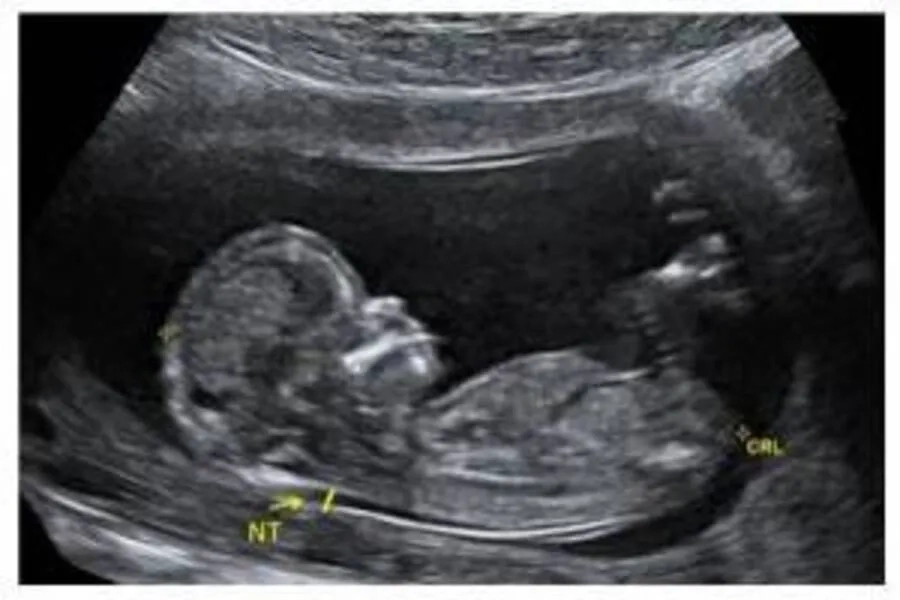

Song song với xét nghiệm máu, bác sĩ tiến hành siêu âm đo độ mờ da gáy (NT) của thai nhi. Độ dày mô sau gáy lớn hơn bình thường có thể liên quan đến nguy cơ dị tật nhiễm sắc thể. Kết quả xét nghiệm máu sẽ được kết hợp với thông tin từ siêu âm và yếu tố nguy cơ của mẹ (tuổi, tiền sử sản khoa) để tính toán xác suất thai nhi mắc bất thường.

Ở bước này, bác sĩ sẽ tiến hành siêu âm để kiểm tra sự phát triển của thai nhi, xác định chính xác tuổi thai và đo các chỉ số quan trọng như chiều dài đầu mông (CRL), độ mờ da gáy (NT), tim thai. Những thông tin này không chỉ giúp đánh giá tình trạng phát triển sớm của thai, mà còn là dữ liệu cần thiết để kết hợp với kết quả xét nghiệm máu, từ đó tính toán nguy cơ bất thường nhiễm sắc thể chính xác hơn.

Siêu âm đo độ mờ da gáy khuyến nghị thực hiện từ trong khoảng tuần thai thứ 11 đến 13 tuần 6 ngày

Bước 3: Phân tích và kết hợp kết quả

Sau khi có kết quả xét nghiệm máu, bác sĩ sẽ tiến hành phân tích và kết hợp với các thông số siêu âm như tuổi thai, chiều dài đầu mông (CRL) và độ mờ da gáy (NT). Tất cả dữ liệu này được đưa vào phần mềm chuyên dụng để tính toán xác suất thai nhi có nguy cơ mắc các rối loạn nhiễm sắc thể như Down, Edwards hay Patau.